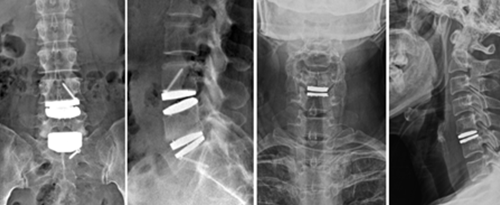

여러 가지 신체적인 작용으로 경추와 요추에 나타나는 요통, 디스크, 관절염,

골다공증, 척추협착증, 척추변형증, 디스크탈출증 등으로 통증이

나타나 활동에 어려움을 겪고 있습니다.

요통, 경추통, 방사통, 척추 골절, 척추 디스크, 척추관협착증, 척추전방전위증,신경차단술, 척추신경성형술, 내시경하 수핵제거술, 척추고정유합술 등

요통, 경추통, 방사통, 척추 골절, 척추 디스크, 척추관협착증, 척추전방전위증, 신경차단술, 척추신경성형술, 디스크고주파 감압술, 양방향 / 단일공 내시경하 수핵제거술, 척추 풍선복원술, 경추/요추 퇴행성질환 교정술 등